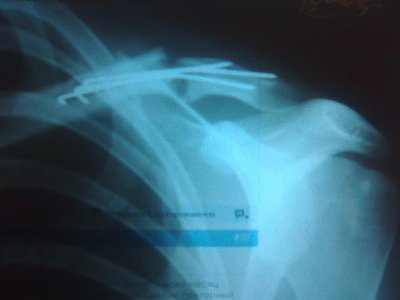

Сегодня сделала очередной рентген, вообще ничего хорошего он не показал. После операции прошло 8 месяцев, сращением перелома и не пахнет. Чувствую себя чем дальше, тем лучше. Врач говорит ждать, а я уже стала сомневаться, заживет ли он вообще (прилагаю сегодняшний снимок, извините за плохое качество).

В чем может быть проблема столь долгого несращения? Есть ли шанс, что, если оставить все как есть, он все-таки срастется? Может проблема в имплантанте? Стоит ли обращаться к другим специалистам?

Зображення126.jpg